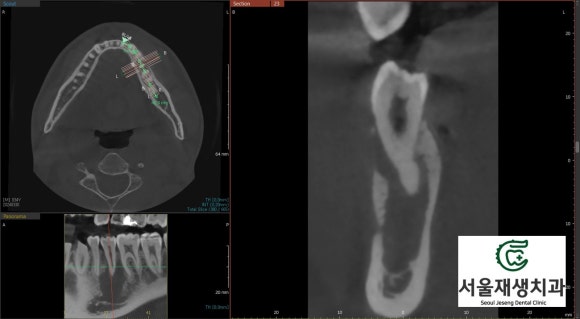

치료 시작하고 두 달 남짓 지났을 무렵...

신경치료를 시작하고 한 두 달 정도 지나면,

CT를 통해서 뼈의 재생 여부를

관찰할 수 있습니다.

이 환자분은 두 달 정도 되었는데요,

한 번 CT를 찍어볼까요?

![[치외치신경치료] 뿌리 끝 염증이 커서 발치해야된대요! 치아 머리에 볼~록! 알고보면 무서운 작은 혹 (서울재생치과) 관련 이미지 19](https://pub-9f2bb3498faf4d1d8714b41df24753e3.r2.dev/content/clinics/archive/nqmm0udu86/naver_blog/honeybeevuvu/assets/by_hash/06f6bb597a645324562c2dcd3b7ed8416d8442eea8b2f1a2295f2e40049af2c4.jpg)

꽤나 드라마틱한 변화!!!

잘 모르시겠다구요?

![[치외치신경치료] 뿌리 끝 염증이 커서 발치해야된대요! 치아 머리에 볼~록! 알고보면 무서운 작은 혹 (서울재생치과) 관련 이미지 20](https://pub-9f2bb3498faf4d1d8714b41df24753e3.r2.dev/content/clinics/archive/nqmm0udu86/naver_blog/honeybeevuvu/assets/by_hash/3ee73b4a70f6df6e42f4c25d24593391de91da23d380daed9f89783da5d8f5bd.jpg)

노란색으로 표시된 부위가

새로이 뼈가 재생된 공간입니다.

신생골은 아직 석회화가 부족해서

초기엔 옅은 회색으로 보인답니다.

이정도면 아주 충분합니다!

다음 달에 치료를 마무리합시다~^^